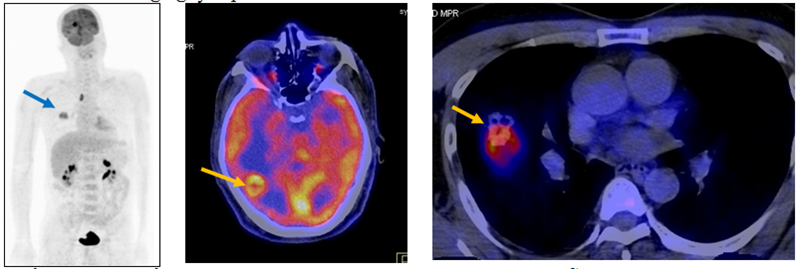

Ca lâm sàng 2: Bệnh nhân nam, 49 tuổi, chẩn đoán: Ung thư di căn não chưa rõ nguyên phát, chụp PET/CT để tìm tổn thương nguyên phát.

Hình 2: khối u ác tính phổi phải di căn hạch, di căn não (mũi tên). Giải phẫu bệnh sau chụp PET/CT là ung thư biểu mô tuyến.